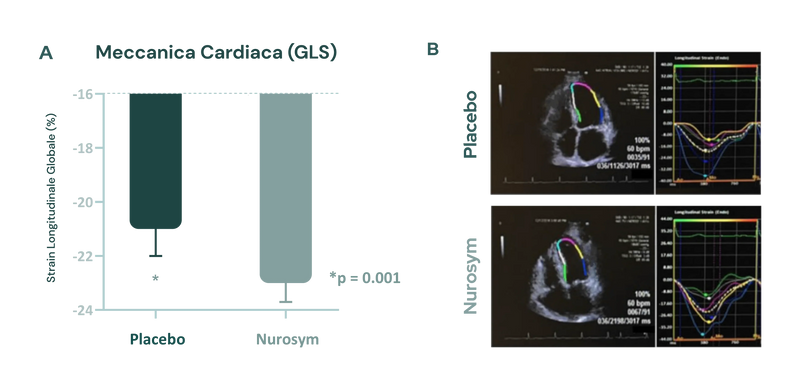

Dopo 3 mesi di trattamento con Nurosym, è stata osservata una riduzione della deformazione del muscolo cardiaco (indicata dal miglioramento del GLS (funzione ventricolare sinistra) di circa l'11% rispetto al gruppo di controllo, e questo miglioramento è stato associato a una riduzione dei fattori di rischio di malattie cardiovascolari (doi: 10.1161/JAHA.121.023582).

Fig. Cambiamenti nella deformazione longitudinale globale (GLS). La neuromodulazione Nurosym indica un miglioramento significativo del parametro GLS rispetto al placebo (*P<0,05) (Parasym Clinical Trials, doi: 10.1161/JAHA.121.023582).

Un'altra ricerca ha concluso che Nurosym migliora acutamente la meccanica cardiaca modulando il tono autonomo (doi: 10.1007/s12265-018-9853-6).

Fig. (a, b) L'applicazione della neuromodulazione attiva Nurosym ha portato a una riduzione della deformazione longitudinale globale, rispetto alla stimolazione sham. Un esempio reale di analisi delle deformazioni del ventricolo sinistro (come visto nella vista apicale a 4 camere) ha mostrato che la neuromodulazione Nurosym (pannello inferiore) ha avuto un impatto positivo rispetto alla stimolazione sham (pannello superiore) sullo stesso paziente (doi: 10.1007/s12265-018-9853-6).